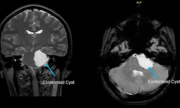

Người phụ nữ 52 tuổi ở miền Tây bị đau đầu liên tục, mỗi lần như vậy bà mua thuốc uống và thuyên giảm. Đến lúc nhập viện thì bác sĩ phát hiện có "kẻ" khổng lồ trong não người phụ nữ này.